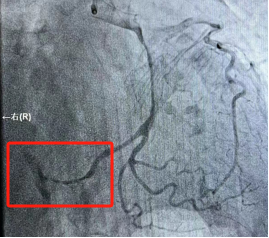

2023-10-19_勇攀“心”高峰——记商城县人民医院心血管内科介入能力再突破!_6.jpg

右冠脉细小,未见明显狭窄